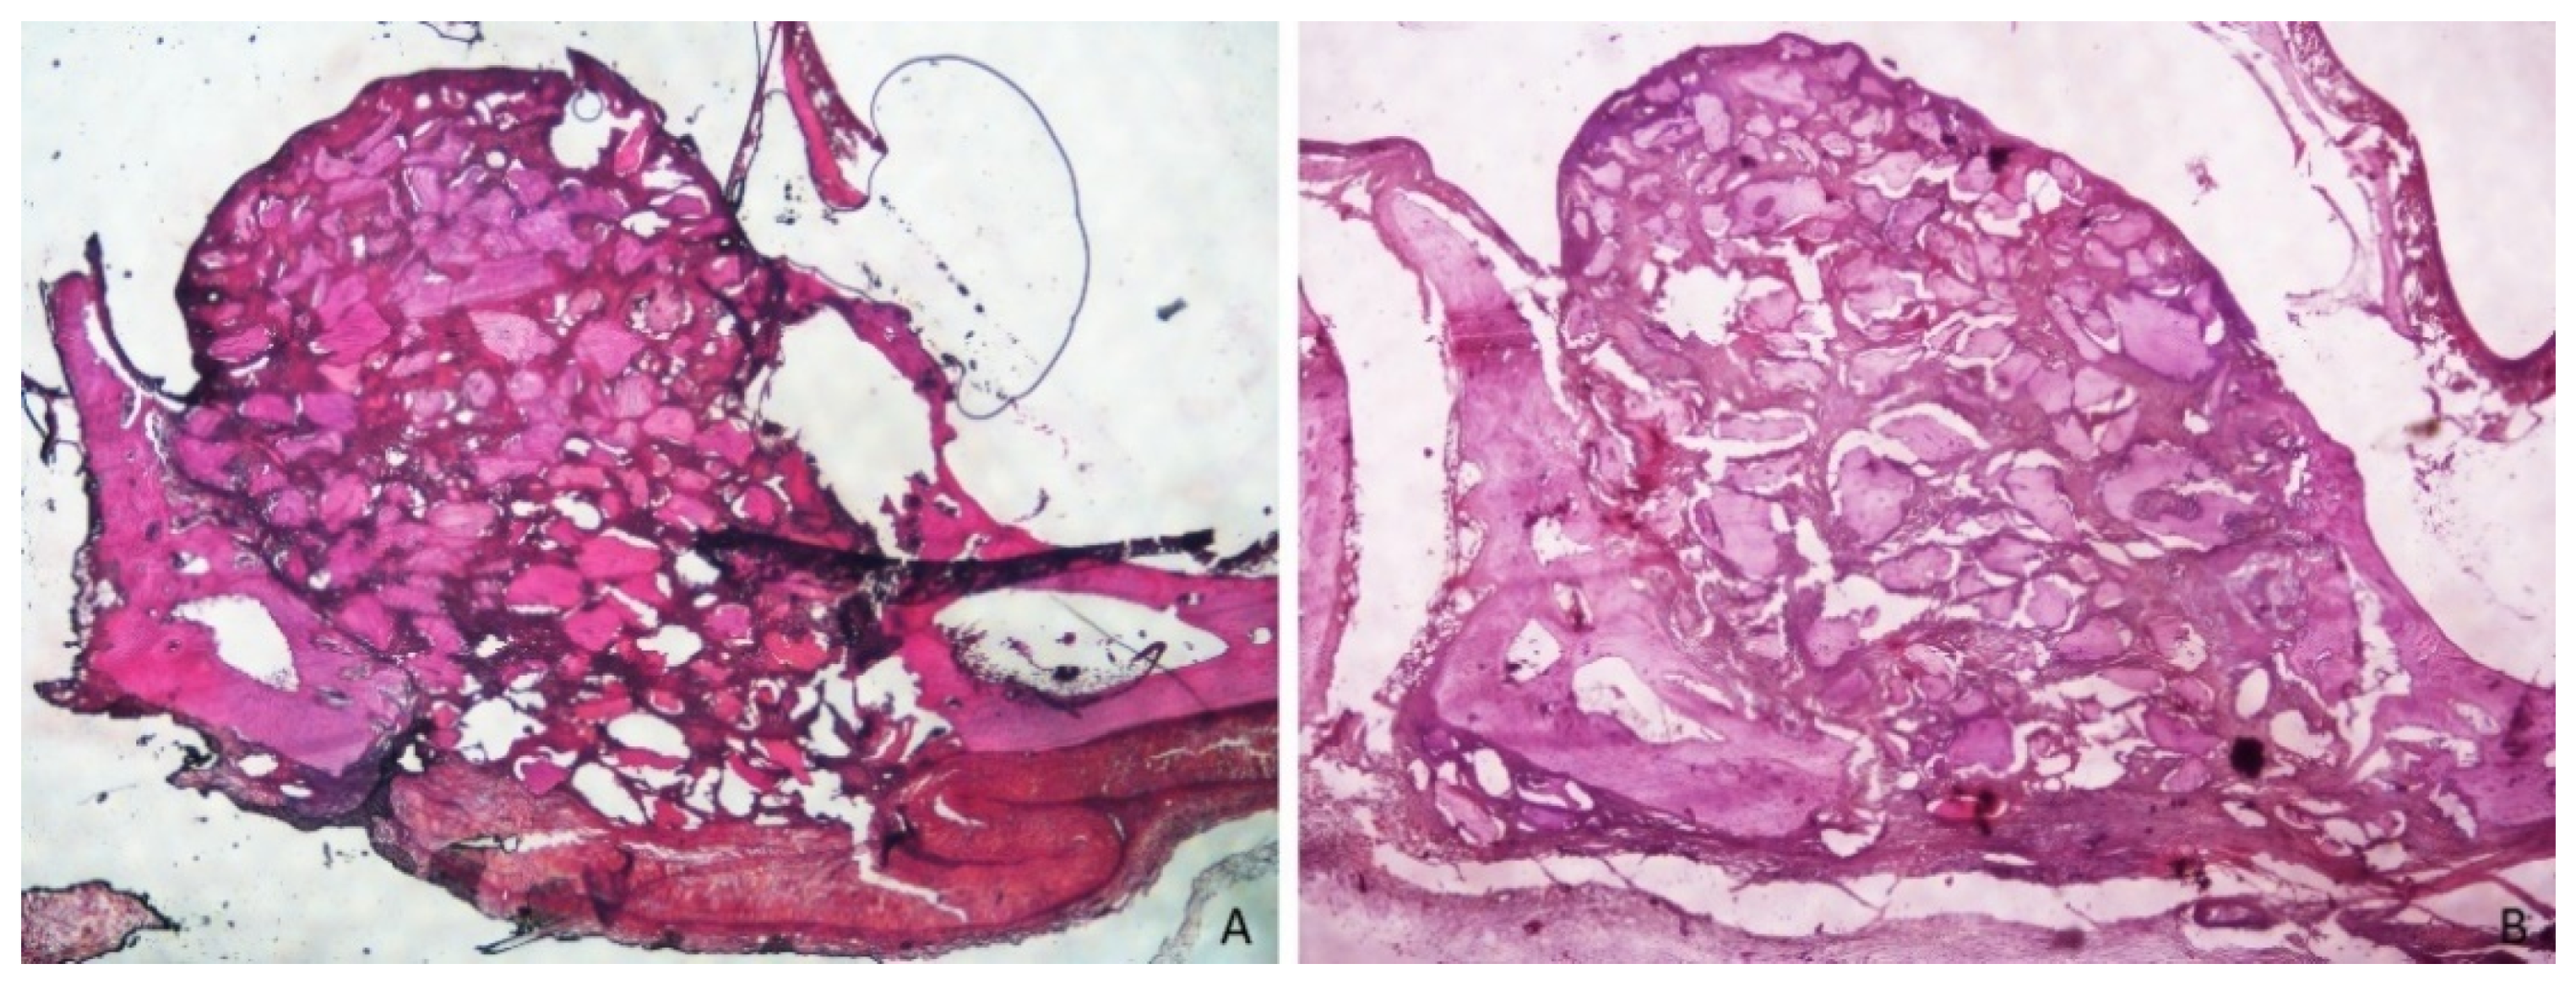

3.1. Grafted Region

3.2. Osteotomy Region